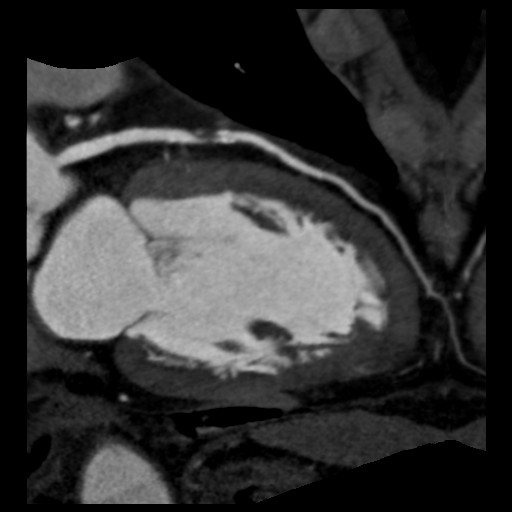

CTで撮影した画像

冠動脈狭窄

心臓の冠動脈や脳・頚部血管疾患の診断に威力を発揮します。

この撮影範囲:16cmを使用すれば、頭部や心臓をはじめ、臓器でも1回転の撮影で検査を終えてしまいます。心臓検査は175msecの分解能で、頭部ではダイナミック検査で虚血部位を、さらに臓器では血管の造成・生成を確認して治療方法を、それぞれ確認することが可能です。